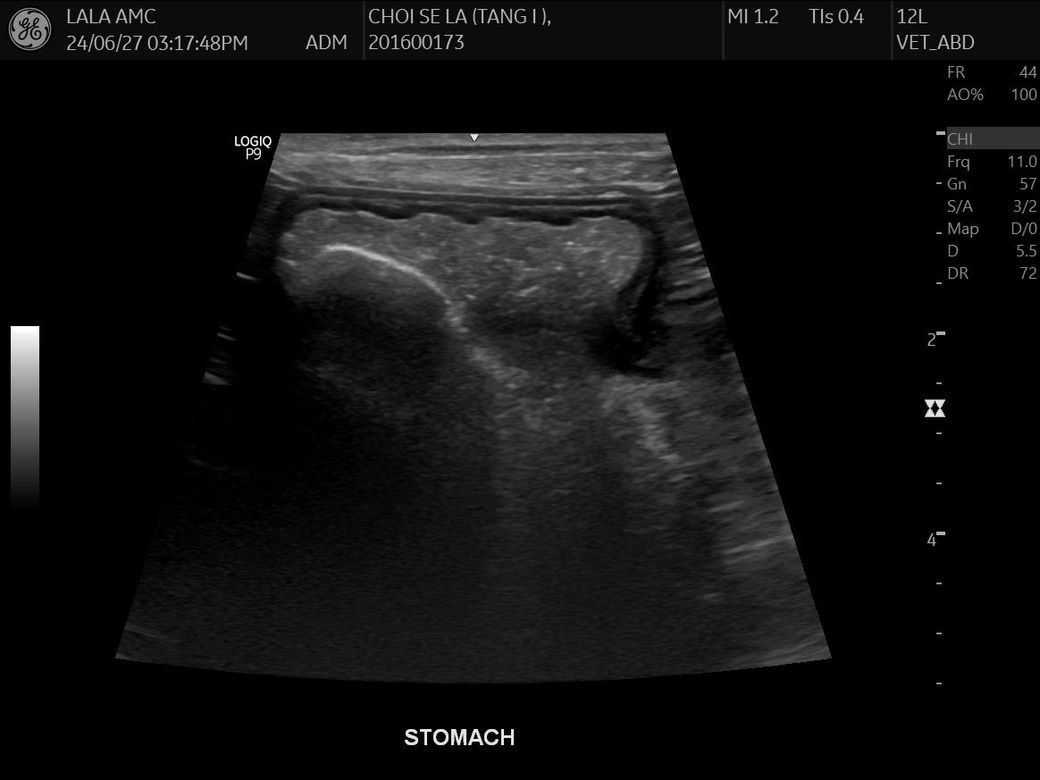

건강검진 하면서 초음파를 찍었는데

강아지 몸속에 1.8cm 물체인지 뭔가가 보인다고 합니다 건강검진은 아무이상 없었구요

자세한건 내시경을 해야한다고하네요..

저것만봐서는 물체가 있는것같나요?

크기와 반사 계면의 강도, 모양을 볼때 자두씨로 판단됩니다. 내시경을 통해 십이지장으로 넘어가기 전에 꺼내주는걸 추천합니다.